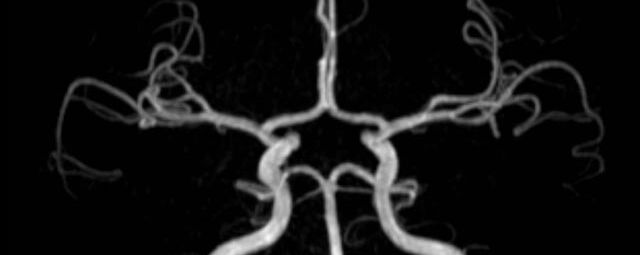

• intrakranielle Gefäße (Abklärung Verschluss, Stenose, Aneurysma)

• Halsgefäße zur Therapieplanung (z.B. Stent, Operation)

MR-Angiografie (MRA)

Angiographie ohne Kontrastmittel

• MR-Angiografie ohne Kontrastmittel

• Time of Flight (TOF)-Angiographie

• Phasenkontrastangiographie (PCA). Geeignet zur Quantifizierung Stenose-/Insuffizienzgrad z.B. bei Herzklappen, falls echokardiographisch die Untersuchungsbedingungen eingeschränkt sind.

Je nach Fragestellung und Körperregion Gefäßdarstellung ohne Kontrastmittel bei Kontrastmittelunverträglichkeit oder terminaler Niereninsuffizienz möglich.